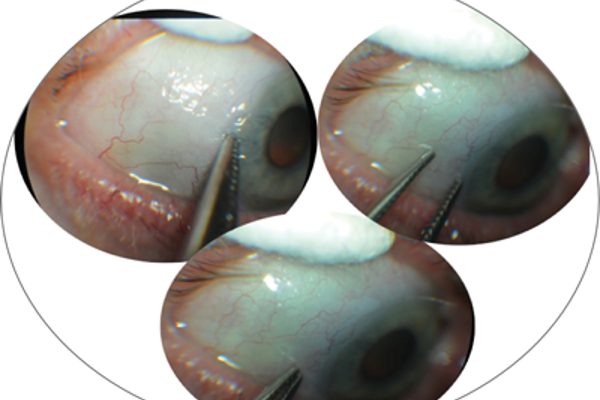

Severe conjunctival cicatrisation secondary to chronic glaucoma therapy